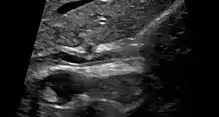

| Cholangiogram of primary sclerosing cholangitis. | |

Various forms of gallbladder disease such as gallstones and gallbladder polyps are also common in those with PSC.[1] Approximately 25% of people with PSC have gallstones.[1] Ultrasound surveillance of the gallbladder every year is recommended for people with PSC.[1] Any person with PSC who is found to have a mass in the gallbladder should undergo surgical removal of the gallbladder due to the high risk of cholangiocarcinoma.[1] Osteoporosis (hepatic osteodystrophy) and hypothyroidism are also associated with PSC.